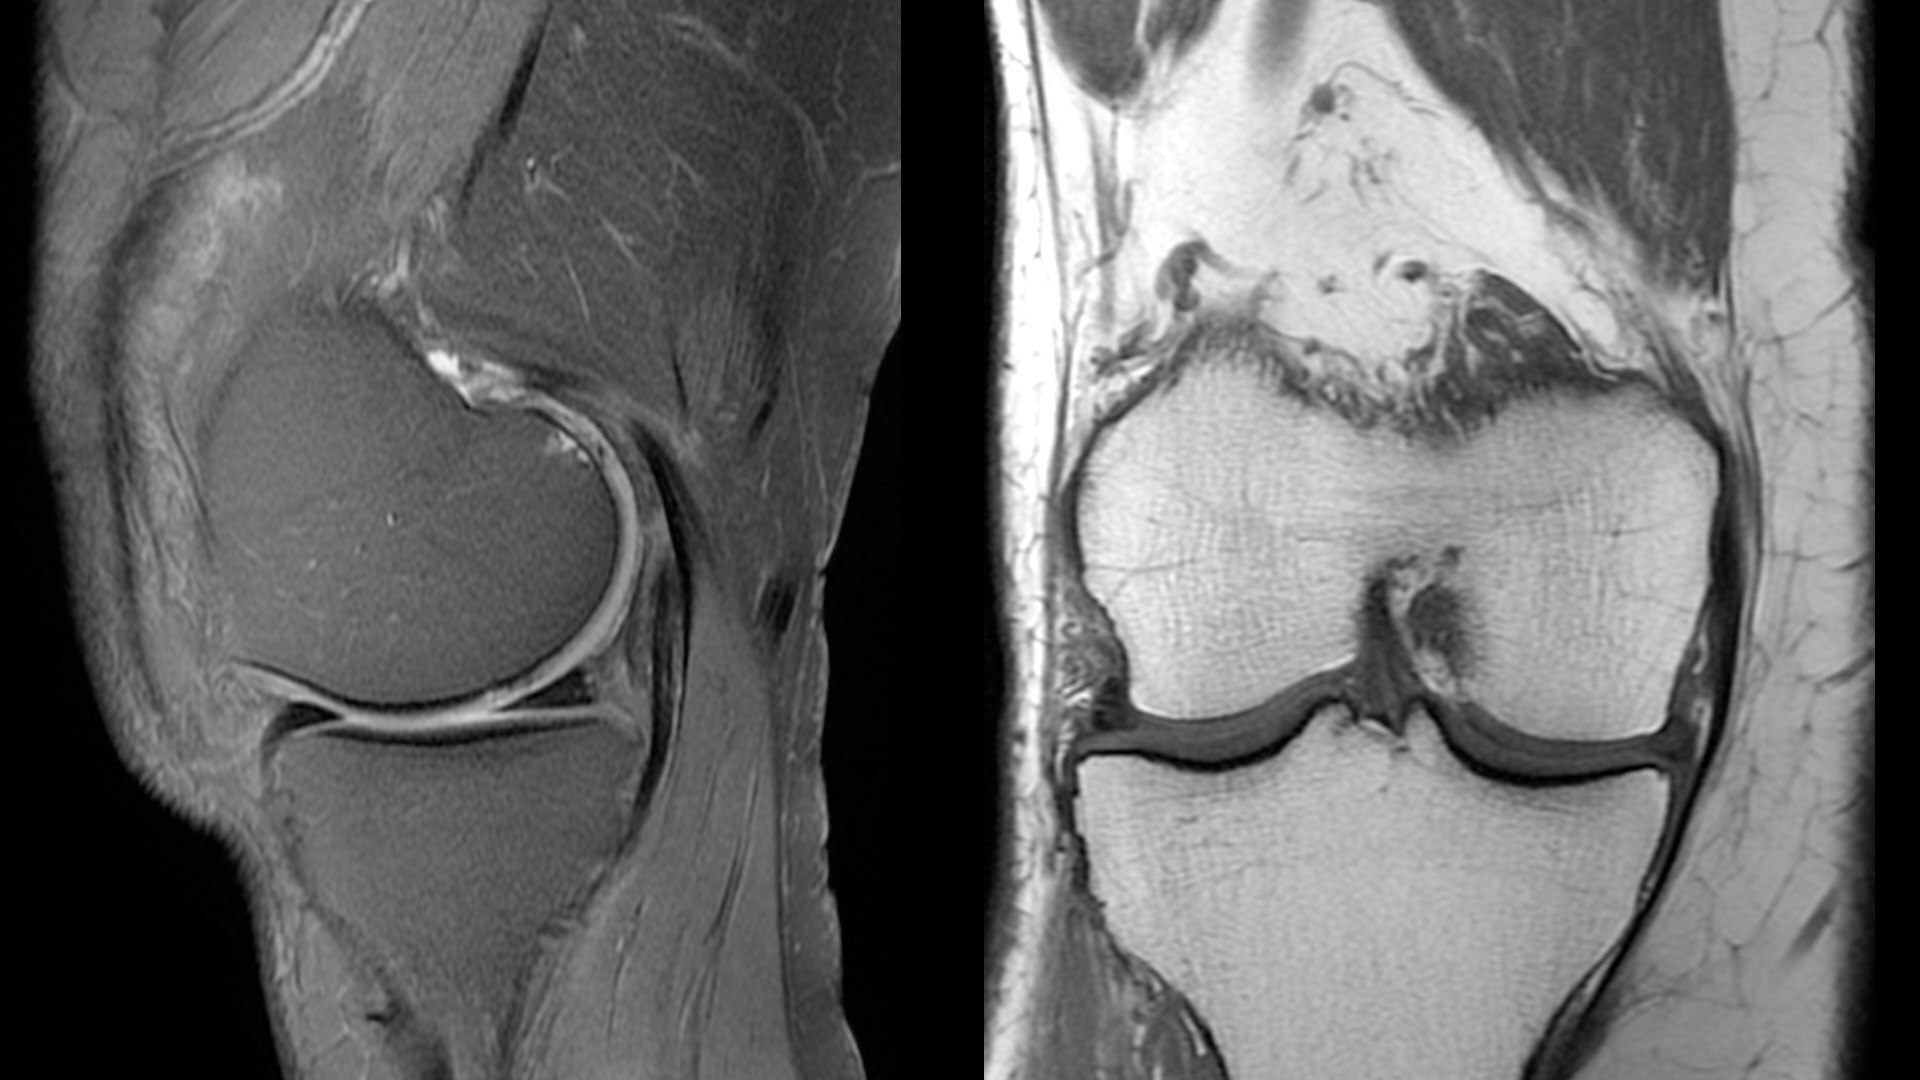

An award-winning industry first in MRI coils. With overlapping, ultra-light, flexible coil elements at their heart, AIR™ Coils deliver an MRI experience that gets closer to your patient, so you get closer to the truth. Representing a new standard in MRI coil technology, AIR™ Coils enable a simplified, faster workflow while maintaining excellent image quality. Scan complex anatomies and complicated conditions in a variety of patient sizes with exceptional results.

The shape of the MRI coil no longer determines what you can do with it. Wrap it around a knee for a complete knee image. Drape it over the patient's body. With an adaptive AIR™ Coil that is light, form fitting and easy to position, it’s the closest you can get to total positioning freedom with 360-degree coverage.

• 360 degrees of coverage for MSK imaging

• 38% lighter per channel compared to previous generations of conventional coil technology

• Increased acceleration compared to previous generations of conventional coil technology

• Positioning freedom with previously hard-to-scan anatomies

• 20-ch and 21-ch design to accommodate all patient sizes and anatomies